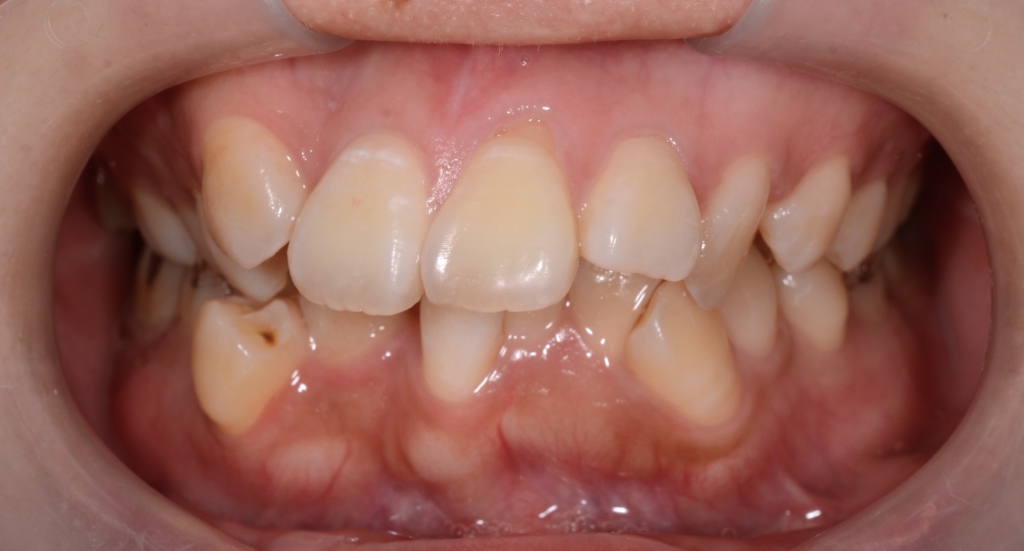

デコボコで出っ歯な歯並びをきれいにしたい!

患者さんは、20代の女性(社会人)です。

「デコボコの歯並びをきれいにしたい!

出っ歯も引っ込めたい!”

そして、できる限り口元も引っ込めたい!」

合わせて上の前歯の真ん中が顔面正中から大きくズレているのも治れば嬉しい。。。

という希望でした。

#1.歯と顎の不調和による叢生(重度)

#2.上顎前突